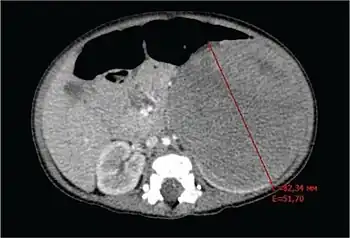

- Imaging studies